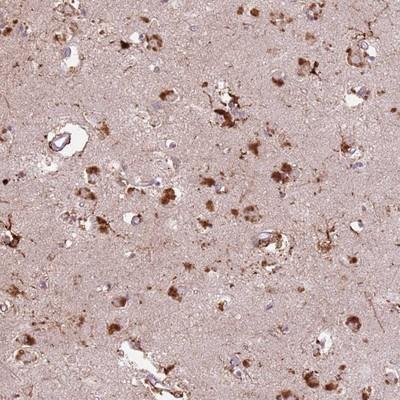

- Main image

- Experimental details

- Immunohistochemistry-Paraffin: C15orf58 Antibody [NBP2-14379] - Staining of human lateral ventricle shows strong cytoplasmic positivity in neuronal and glial cells.